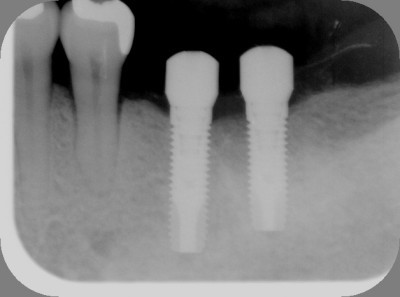

インプラントの術前・術後 Nさん